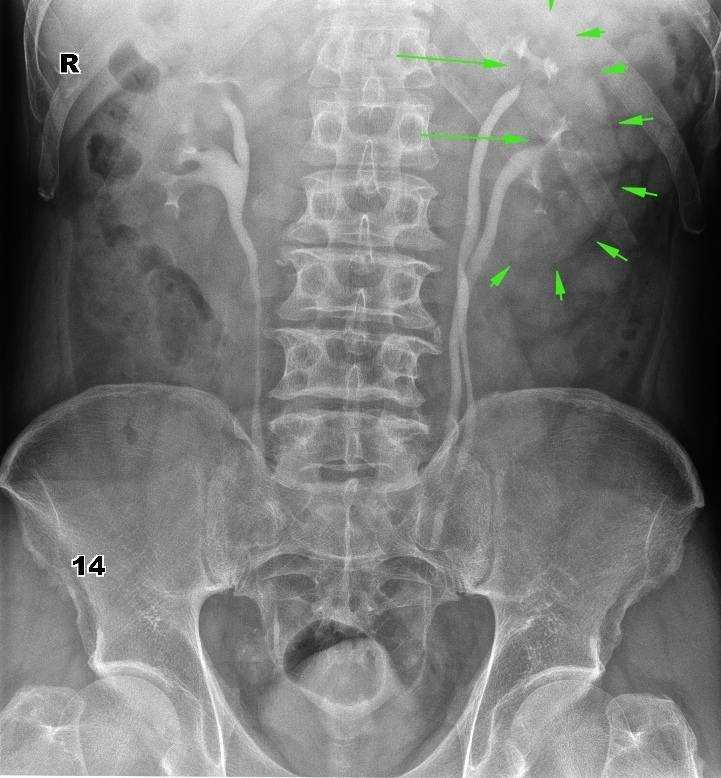

Рентген поясницы: анатомические особенности и медицинские исследования

Раздел: Фотоэссе